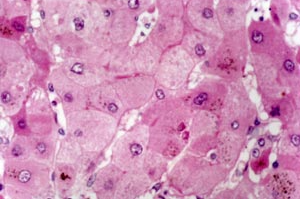

丙型病毒性肝炎是严重威胁人民健康的公共卫生问题。目前尚无预防丙型肝炎病毒(HCV)的疫苗,但直接抗病毒药物(DAA)联合治疗可以治愈95%以上的慢性丙型病毒性肝炎。加强HCV感染者的筛查,针对确诊HCV感染者尽早进行有效的治疗,是消除传染源,阻断HCV传播的有效措施。

丙型病毒性肝炎